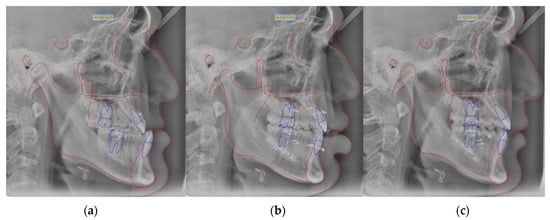

2.2. Study Methods

2.4. The Manufacturing Process of Clear Aligners by CAD/CAM